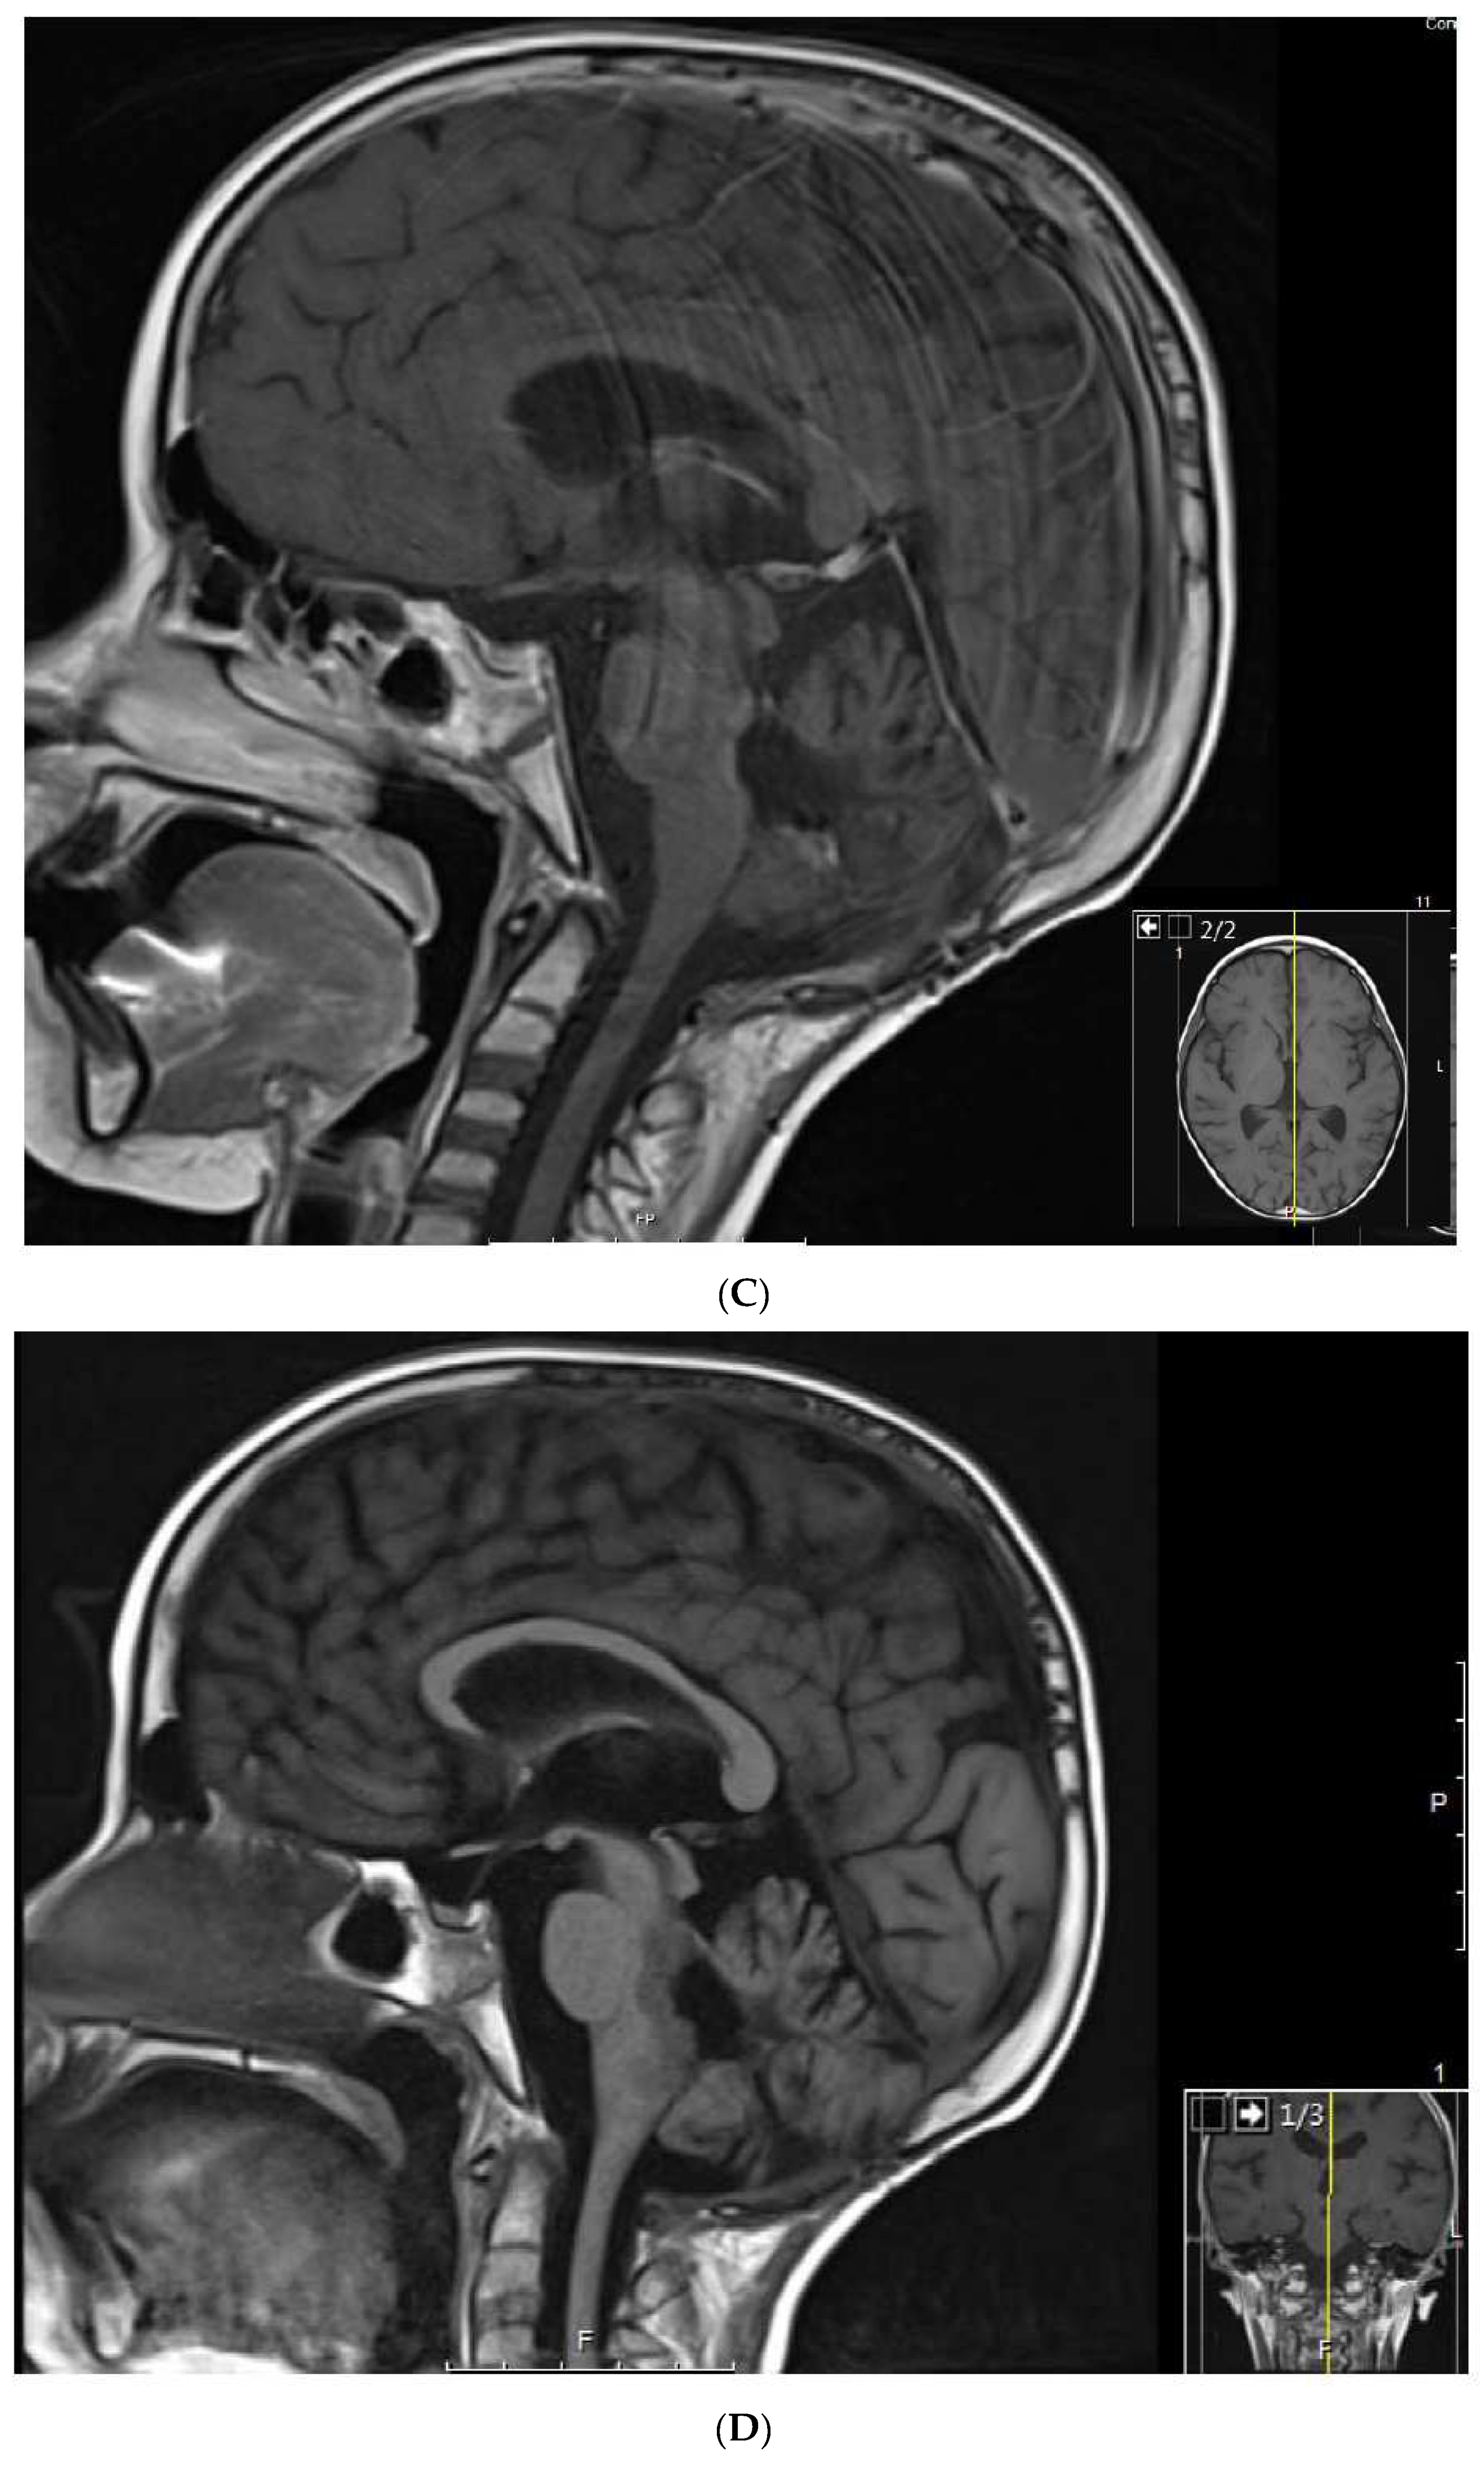

1.3. Patient 3

| 3 | Medulloblastoma Infratentorial Microscopic leptomeningeal relapse | VP16 alone (VA added later) | 10 months | CR | CR 5 years at last encounter Alive 7 years at last encounter |